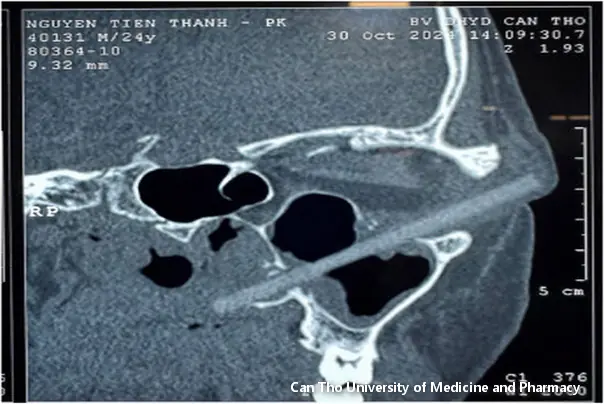

Naknadni regdenski snimak pokazao je da mu je strano telo dužine 9 cm ušlo u očnu duplju.

Brzim pregledom otkriveno je da se čini da je misteriozni predmet drveni štapić za jelo koji je prodro iz mekog tkiva van leve orbite, kroz gornji zid maksilarnog sinusa, i uništio bočni zid nosa.